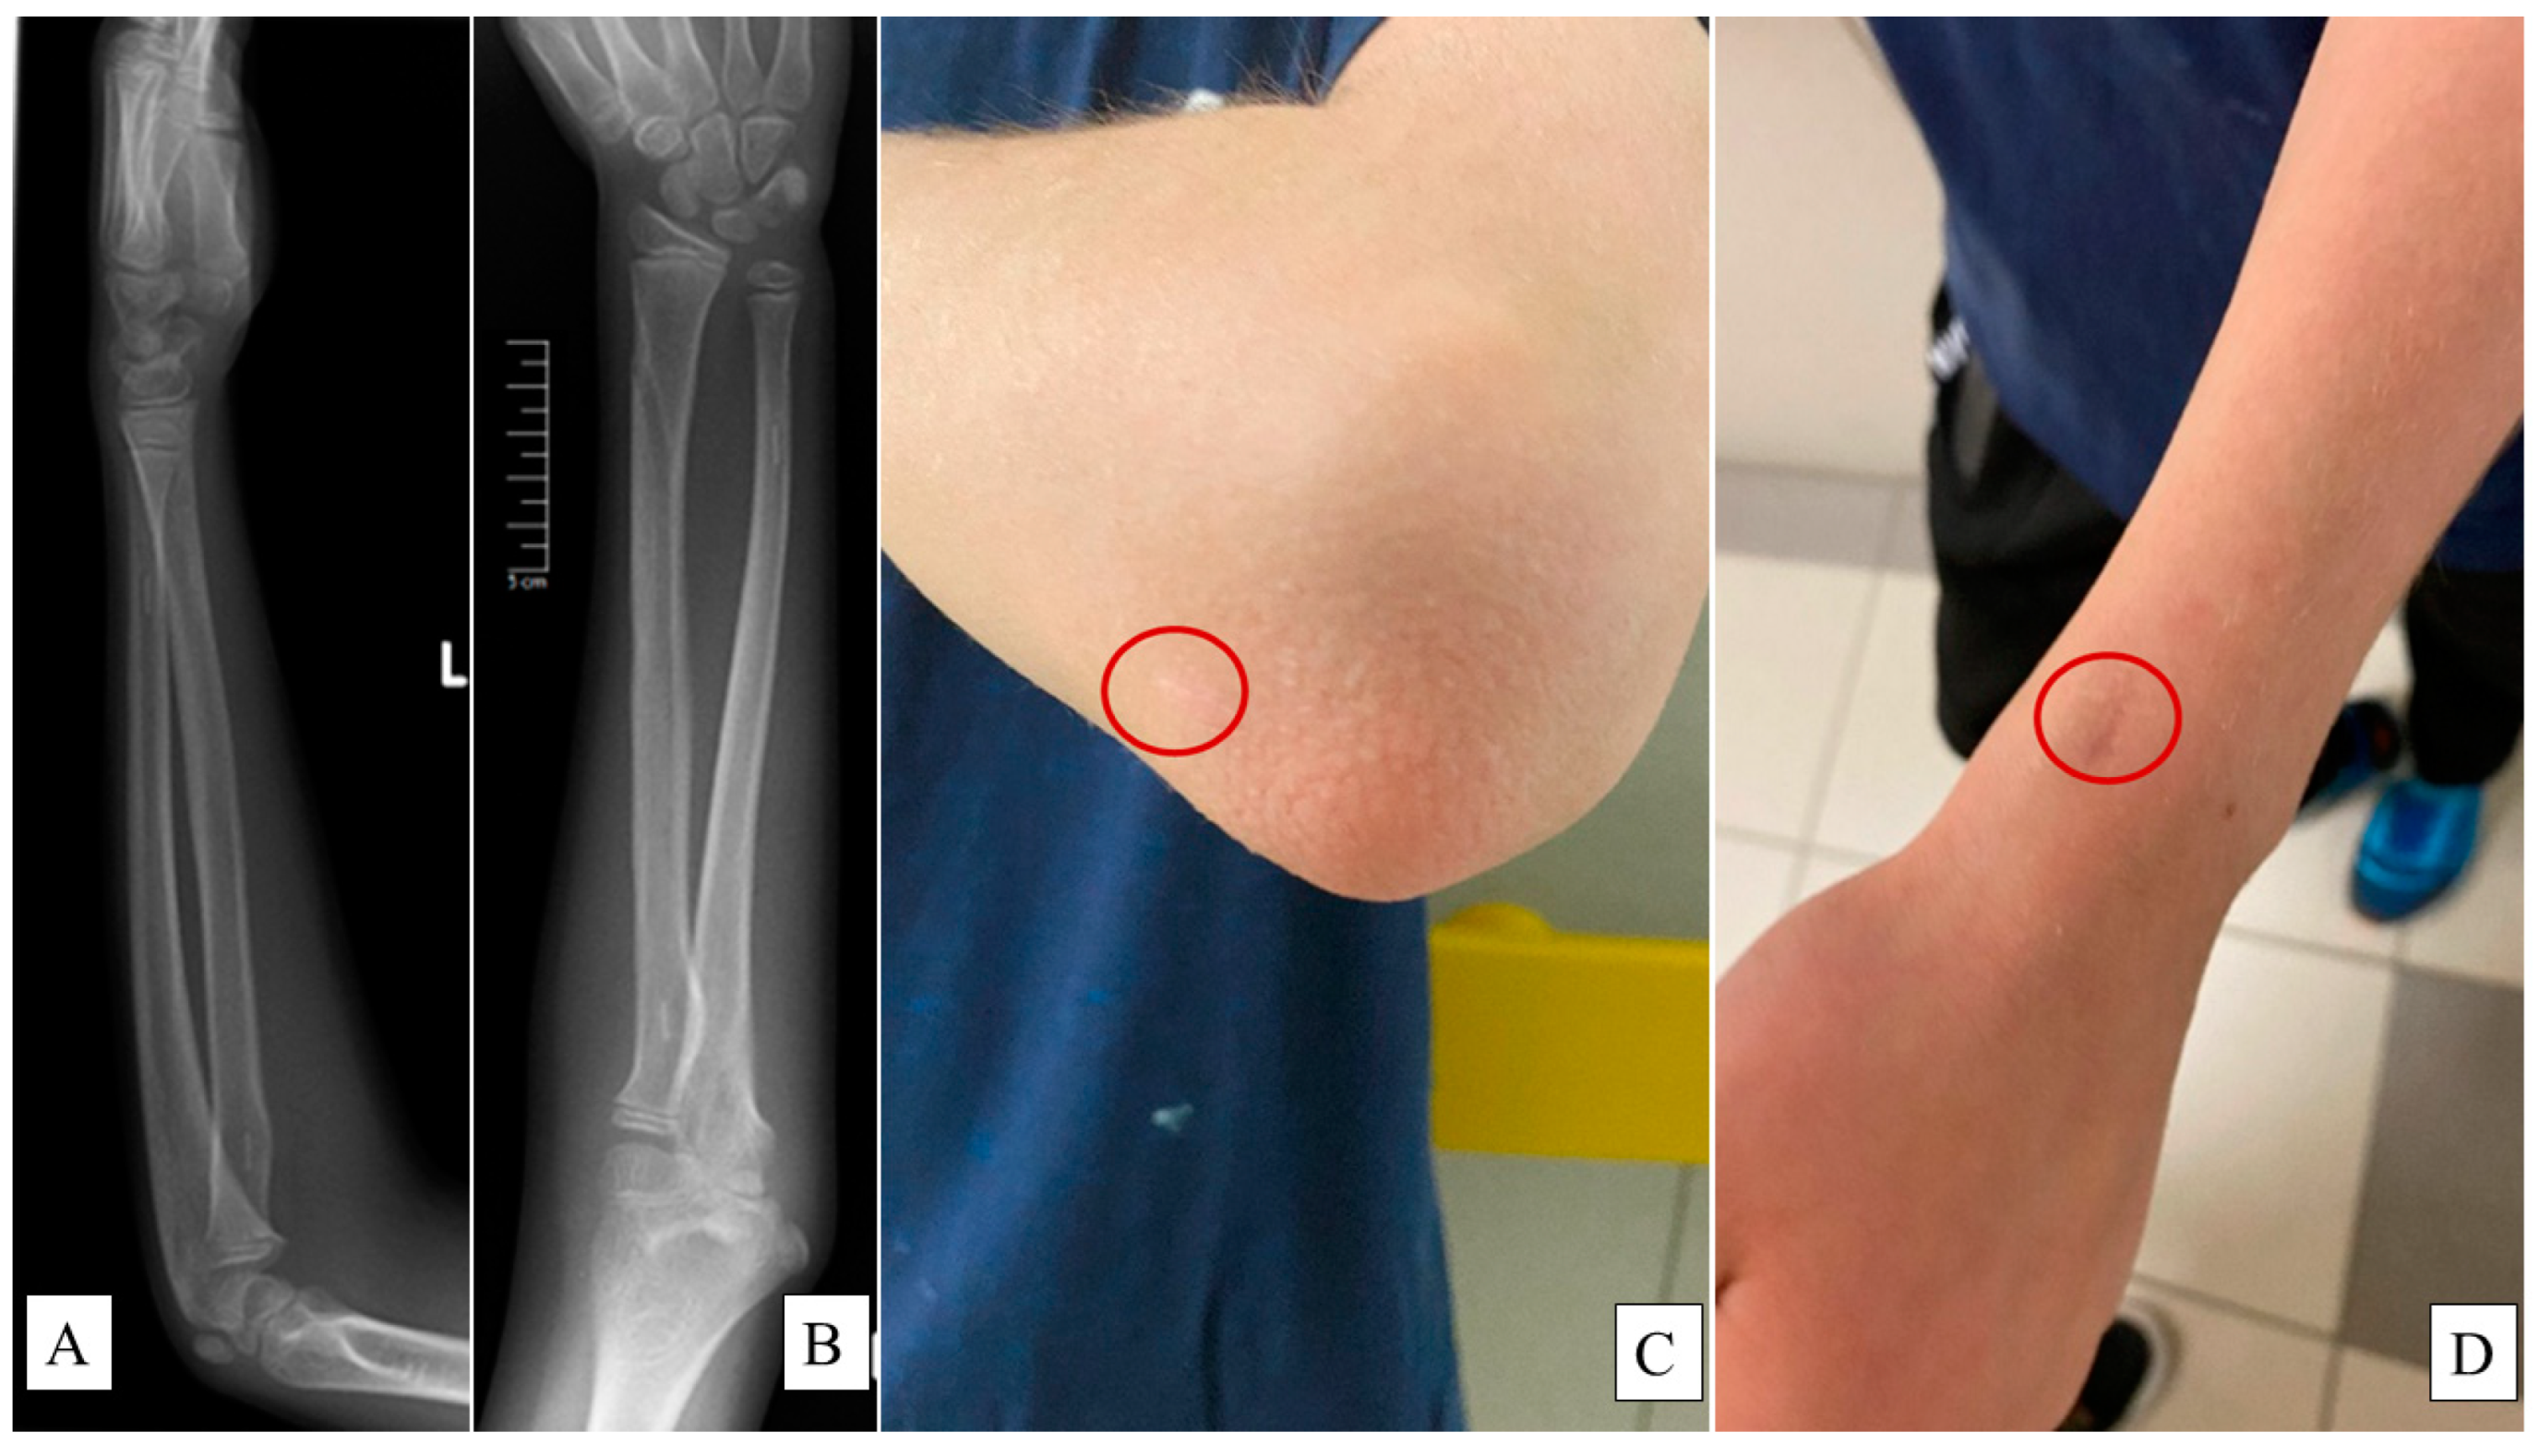

• Elbow flexion and extension: Normal range is −10 to 150 degrees (°). Patients were instructed to fully extend and flex their elbows while standing with arms at their sides (Figure 2).

Figure 2. Elbow extension (A) and flexion (B) of the uninjured arm of an 11-year-old boy. One year after surgery, the operated arm’s cubital extension (C) and flexion (D) demonstrate intact functionality.